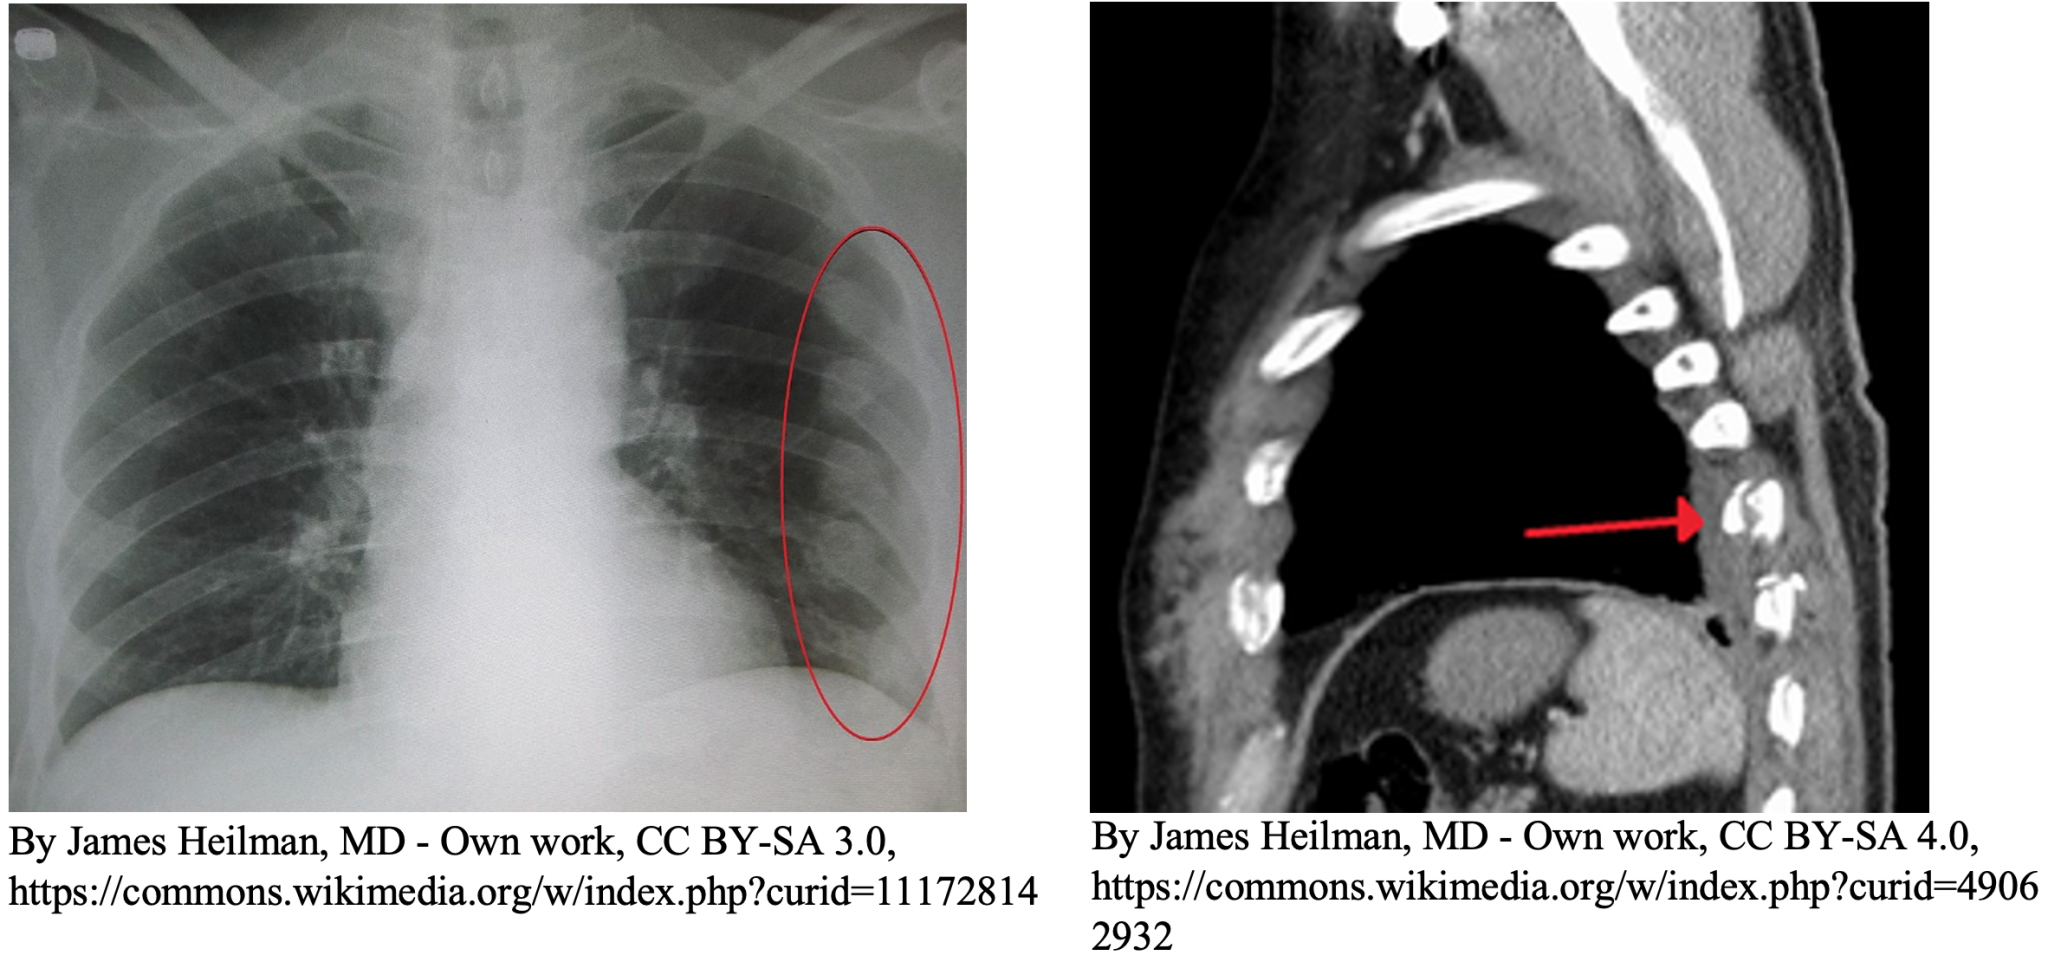

Chest Xray Film of a Patient with Multiple Rib Fractures Stock Photo Rib Fracture Emergency  The following patients who have rib fractures identified on an outpatient radiograph should be referred to the emergency. Rib fractures are very common and are detected in at least 10% of all injured patients, the majority of which are as a consequence of blunt thoracic trauma (75%) with road traffic. Although they are more likely to occur from blunt trauma. Rib Fracture Emergency.

fracture. FRACTURED RIB ON CT SCAN YouTube Rib Fracture Emergency  These guidelines aim to ensure that adult patients admitted with chest trauma, receive optimal treatment and pain relief from admission to. You're coughing up yellow or green mucus; Rib fractures can be a common painful ailment after any trauma. Although they are more likely to occur from blunt trauma (eg,. Typically, this causes pain on. Rib fractures are markers of. Rib Fracture Emergency.